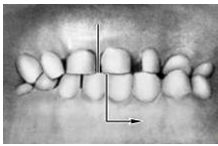

Рис.3. Схема прорезывания постоянного зуба, замещающего молочный . 1- эмаль, 2 -дентин, 3 - пульпа, 4 - остеокласты. Закладка постоянных зубов происходит в начале 5 мес внутриутробного развития. Зачаток постоянного ЗБ находится позади зачатка молочного. Когда прорезываются молочные ЗБ в зачатках постоянных происходит образование эмали и дентина. В процессе замены рост постоянного ЗБ и давление его эмали на корень молочного приводит к рассасыванию остеокластами более мягкой ткани - дентина молочного зуба. Последний выталкивается и заменяется постоянным. 3. Прикус Прикус (occlusio) — соотношение зубных рядов при наиболее плотном смыкании зубов. Смыкание зубов верхней и нижней челюстей при различных движениях последней называется окклюзией. Откусывание и прожевывание пищи сопровождаются различными видами окклюзий. Откусывание осуществляется при передней (сагиттальной) окклюзии, когда смыкаются передние зубы, а боковые разобщаются (между ними появляется просвет). При жевательных движениях возникают боковые (трансверзальные) правая и левая окклюзии. Исходным и заключительным положением для всех жевательных движений нижней челюсти являются центральная (вертикальная) окклюзия, при которой линия, проходящая между центральными резцами обоих зубных рядов, совпадает со срединной линией лица. Вид П. определяется характером смыкания зубных рядов в положении центральной окклюзии, что зависит от формы и размеров зубов, их количества и места в зубных рядах, а также от размеров челюстных костей и их положения. В норме понятия «прикус» и «центральная окклюзия» почти идентичны, т. е. прикусом считают соотношение зубных рядов в состоянии центральной окклюзии. Нормальный, или физиологический, П. характеризуется определенными признаками. Все зубы верхней и нижней челюстей (за исключением третьего верхнего моляра и первого нижнего резца) контактируют между собой таким образом, что каждый зуб смыкается с двумя антагонистами. Каждый зуб верхней челюсти контактирует с одноименным и позадистоящим зубом нижней челюсти, каждый зуб нижней челюсти — с одноименным впереди стоящим зубом верхней челюсти; срединная линия лица проходит между центральными резцами верхней и нижней челюстей и находится с ними в одной сагиттальной плоскости. В зубных рядах промежутки между зубами отсутствуют. Зубные дуги имеют определению форму (верхняя — полуэллипса, нижняя — параболы). Наружная часть верхней зубной дуги больше внутренней части за счет наклона зубов в сторону преддверия рта. наружная часть нижней зубной дуги меньше внутренней части за счет наклона зубов в сторону полости рта. При смыкании зубных рядов формируется окклюзионная кривая. Суставная головка нижней челюсти находится в середине суставной ямки височно-нижнечелюстного сустава. Различают несколько вариантов нормального П. (ортогнатический, прогенический, прямой, бипрогнатический). Они характеризуются смыканием зубных рядов на всем протяжении и отличаются друг от друга лишь особенностями смыкания функционально ориентированных групп зубов, в частности передних. Эталонным принято считать ортогнатический прикус (рис. 5, а), при котором верхний зубной ряд на всем протяжении перекрывает нижний, а во фронтальном участке верхние резцы перекрывают нижние не более чем на 1 /3 коронковой части зуба; между резцами верхней и нижней челюстей имеется режуще-бугорковый контакт. Прогенический прикус (рис. 5, б) отличается умеренным выстоянием нижнего зубного ряда. Прямой прикус (рис. 5, в) характеризуется тем, что верхние резцы не перекрывают нижние, а смыкаются режущими краями. При бипрогнатическом прикусе (рис. 5, г) верхние и нижние резцы наклонены в сторону преддверия рта, но между ними сохранен режуще-бугорковый контакт. Для всех вариантов нормального прикуса обязательным условием является нормальное функционирование зубочелюстной системы. Патологический П. формируется при аномалиях зубов и челюстей врожденного или приобретенного характера (пародонтоз, пародонтит и др.). Основным отличием патологического прикуса от нормального является нарушение смыкания зубных рядов в различных направлениях вплоть до полного отсутствия на отдельных участках, что приводит к изменению функции зубочелюстной системы. Существует множество классификаций аномалий П., однако общепринятой является международная классификация, предложенная в 1899 г. Энглом (Е.Н. Angle). В ее основе лежит соотношение первых моляров, что, по мнению Энгла, служит ключом окклюзии. В соответствии с классификацией к первому классу (рис. 6, а) относятся все аномалии, при которых первые моляры находятся в правильном соотношении (мезиально-шеечный бугор первого моляра верхней челюсти располагается в межбугорковой фиссуре первого моляра нижней челюсти), а все аномалии П. обусловлены изменениями зубов или челюстей спереди от первых моляров, например при скученности резцов, их протрузии (наклоне в сторону преддверия рта) или ретрузии (наклоне в сторону полости рта). Во второй класс включены аномалии, при которых нарушено смыкание первых моляров и фронтальной группы зубов. Межбугорковая фиссура первого моляра нижней челюсти располагается позади мезиально-щечного бугра первого моляра верхней челюсти, т.е. нарушено смыкание зубов в сагиттальной плоскости (переднезаднем направлении). Подобные нарушения (так называемый дистальный прикус) могут быть обусловлены чрезмерным ростом верхней челюсти (прогнатией) или (реже) недоразвитием нижней челюсти (микрогенией). В зависимости от положения и смыкания фронтальной группы зубов во втором классе выделяют два подкласса: первый характеризуется протрузией резцов (рис. 6, б), второй — их ретрузией (рис. 6, в). Третий класс (рис. 6, г) включает аномалии П., при которых межбугорковая фиссура первого моляра нижней челюсти располагается впереди мезиально-щечного бугра одноименного моляра верхней челюсти (мезиальный П., прогения, прогенический П., антериальный П.). Кроме аномалий П. в сагиттальной плоскости существуют аномалии П. в вертикальной и трансверзальной плоскостях. К основным вертикальным аномалиям (определяются по отношению к горизонтальной плоскости) относится открытый и глубокий П. Открытый П. (рис. 7, а) — наличие щели между зубными рядами при их смыкании, чаще в области передних зубов, реже в области боковых. Иногда смыкаются только последние моляры, что приводит к выраженным нарушениям жевательной функции и особенно речи. При глубоком П. (рис. 7, б) передние зубы одной из челюстей в значительной степени перекрывают коронки зубов-антагонистов, нижние резцы не опираются на зубные бугорки верхних резцов, а соскальзывают к их десневому краю, что приводит к постоянному травмированию десен и неба; нижняя часть лица укорочена за счет уменьшения или дистального положения подбородка. К трансверзальным аномалиям, определяемым по отношению к сагиттальной плоскости, относится перекрестный П. (рис. 7, в), при котором верхний зубной ряд в области боковых участков в значительной степени перекрывает нижний зубной ряд (латерогнатический П.) или нижний перекрывает верхний (латерогенический П.). Кроме перечисленных выше видов патологического П. выделяют так называемый снижающийся прикус, который формируется вследствие стирания зубов или их утраты. При этом нижняя треть лица укорочена, расстояние между зубами увеличено (до 8—10 мм при норме 2—3 мм), углы рта опущены, носогубные складки резко выражены. При потере боковых зубов в детском или юношеском возрасте возможно дистальное смещение нижней челюсти. Снижающийся П., как правило, приводит к изменению соотношения элементов височно-нижнечелюстного сустава, в результате чего могут возникать боли в области сустава, затруднения и асимметрия движений нижней челюсти, щелканье или треск в суставе при его движениях, головные боли, шум в ушах. Патологический П., возникший при уже сформировавшемся нормальном П. в результате заболеваний или утраты зубов, как правило, сопровождается деформацией зубных рядов, смещением отдельных зубов или их групп, иногда вместе с альвеолярным отростком. Аномалии П. определяются при осмотре полости рта. Причину формирования аномалии устанавливают после изучения формы и размеров зубов, зубных рядов, апикальных базисов челюстей с помощью гипсовых моделей челюстей. Размеры челюстных костей и их положение в черепе определяют с помощью телерентгенографии, размеры и формы височно-нижнечелюстных суставов — с помощью томографии. Большое значение имеют функциональные методы исследования мышц челюстно-лицевой области (электромиография, миотонометрия), пародонта (гнатодинамометрия, периотестометрия), височно-нижнечелюстных суставов (аксиография, фонография). Для исправления аномалий П. применяют ортодонтические методы лечения, направленные на изменение формы и нормализацию размеров зубных рядов, их соотношения и окклюзии. При резко выраженных аномалиях П. наряду с ортодонтическими методами применяют и оперативное лечение. При стирании или потере зубов показано протезирование. Лечебные мероприятия при аномалиях прикуса целесообразно начинать как можно раньше с момента их выявления. Большое значение для формирования правильного П. у детей и сохранения его у взрослых имеют профилактические мероприятия, к которым относится выявление детей из групп риска (дети с врожденной патологией или неблагоприятной наследственностью, нарушением носового дыхания и др.), полноценное питание и правильный режим матери в период беременности, введение своевременного при корма, предупреждение рахита и других заболеваний у ребенка, устранение вредных привычек (сосание пальца, языка, щек). Особое место занимают своевременное лечение зубов и восстановление целостности зубных рядов путем их протезирования. В связи с тем что наиболее часто зубочелюстные аномалии возни кают в период смены зубов, дети от 6 до 13 лет нуждаются в особенно тщательном наблюдении.